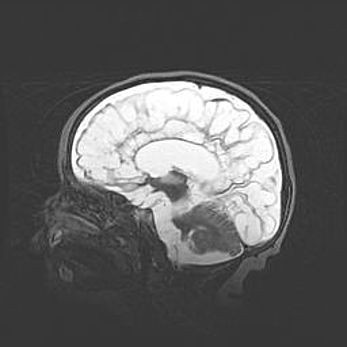

Аномалия Денди-Уокера. Признаки гипоплазии мозолистого тела.

Возраст: 5 месяцев 3 дня

Вес: 5550 г

Пол: мужской

Окружность головы: 39 см

Срок гестации: 40 недель

Аномалия Денди-Уокера – это порок развития головного мозга, для которого характерна триада симптомов: гипотрофия или аплазия червя мозжечка и/или полушарий мозжечка, расширение четвёртого желудочка с формированием ликворной кисты задней черепной ямки, гипертензионная гидроцефалия различной степени.

Гипоплазия мозолистого тела относится к дефектам внутриутробного этапа развития мозговой ткани, возникающим в процессе закладки структур головного мозга, что происходит на начальных этапах развития эмбриона.